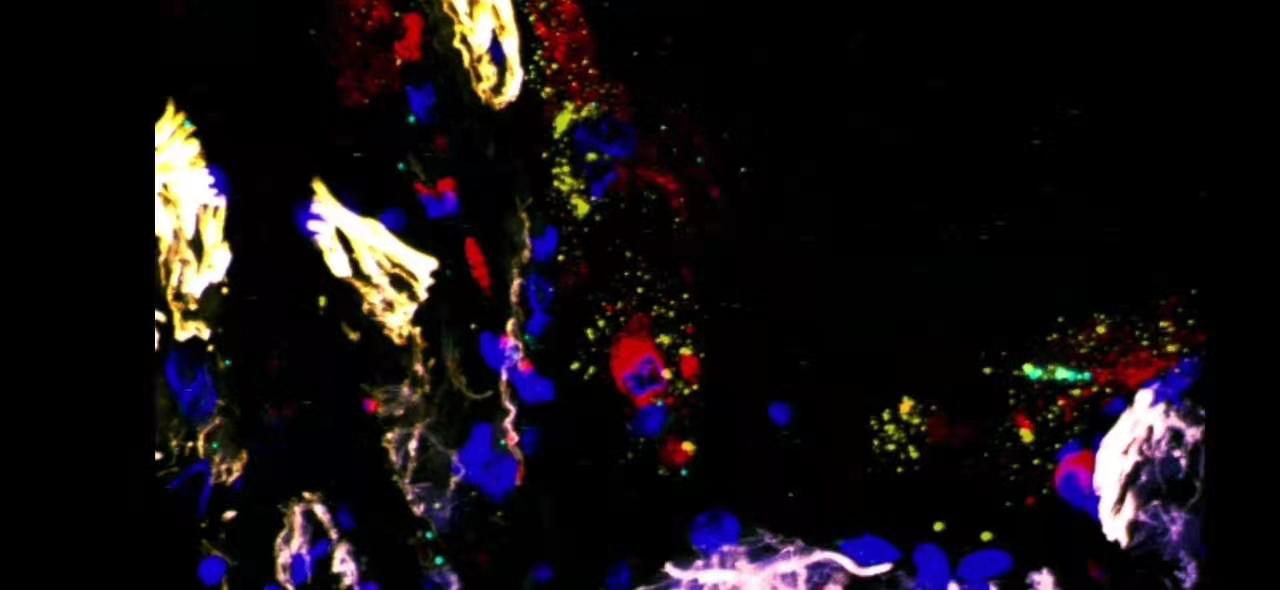

在CD206陽性肺泡巨噬細(xì)胞中檢測SARS-CoV-2陽性和陰性鏈轉(zhuǎn)錄產(chǎn)物。

結(jié)合免疫熒光顯微鏡檢查CD206(一種成熟的巨噬細(xì)胞(紅色))和smFISH(RNAscope)用于SARS-CoV-2陽性(黃色)和陰性(青色)轉(zhuǎn)錄產(chǎn)物。